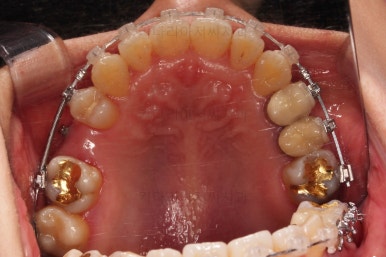

임플란트 할 공간도 여유롭게 마련이 되었네요.

임플란트는 뿌리 부분 식립 -> 3~6개월 기다림(뼈와 임플란트가 단단히 붙을 시간이 필요) -> 머리 부분을 완성하고 마무리

따라서 교정치료가 100% 끝나기 전에, 임플란트 공간만 마련되면 바로 식립을 하게 됩니다.

임플란트 뿌리 부분이 먼저 식립되었고요.

뼈와 잘 붙으라고 잇몸을 잘 꼬메어 줍니다.

최종 보철이 올라갈 3~6개월 기간동안 디테일한 조절을 더 해주고 교정과 임플란트를 동시에 마무리 합니다.

임플란트 보철이 깔끔하게 들어갔고, 교정치료도 마무리가 되었습니다.

화살표 부분은 임플란트가 안들어갔는데요.

약간의 우여곡절이 있긴했었지만 엄밀히 따지면 위아래가 지그재그로 껴들어가는 교합의 특성상 윗니는 1개 모자라도 교합에는 크게 문제가 없답니다.

해당 부분을 임플란트를 해주면 좋겠지만 환자분도 충분히 고민 후에 원하실 때 식립을 하기로 마무리르 하였습니다.